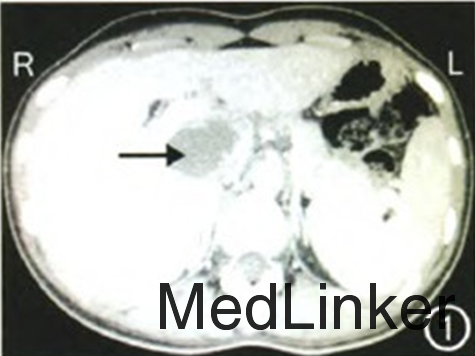

查体:无慢性肝病体征,无腹部压痛、反跳痛,余未见异常。 辅查:肝功能、凝血未见异常,腹部超声检查:肝门部占位性病变;腹上区CT平扫检查:肝门部见混杂密度影,大小约6.3cm×4.2cm,以低密度为主,其内可见多发点状高密度影及分隔(图1);增强CT检查:肝门部病变未见明显强化。